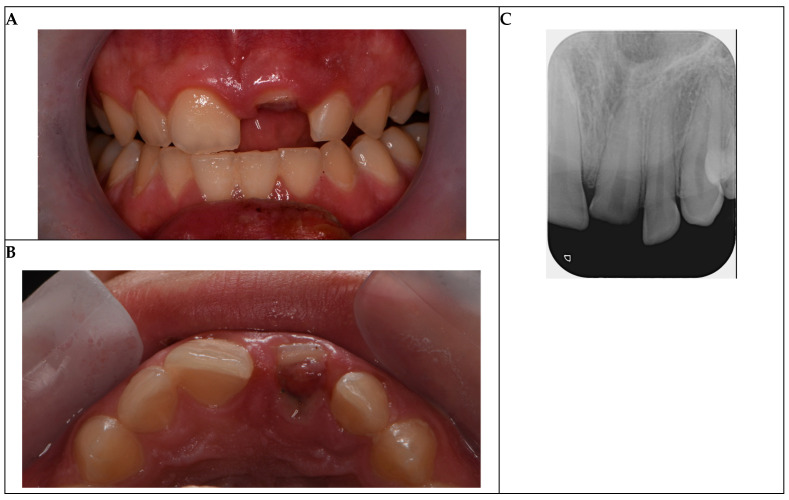

背景与临床意义:外伤性牙损伤,尤其是复杂的恒切牙冠骨折在青少年中很常见,上颌中切牙因其位置突出而最常受影响。这些损伤通常是由运动或意外造成的,需要及时处理,以防止髓质坏死或感染等并发症,这些并发症会影响长期预后。当骨折节段完整时,碎片再附着提供了一种保守、美观的方法,其结果与复合修复相当。本病例报告强调了及时干预和先进的修复技术在儿科牙科的重要性。病例介绍:一名16岁的男性在足球比赛中表现出左上中门牙复杂的冠状骨折。骨折向龈下延伸,牙髓暴露。病人用生理盐水保存碎片。治疗包括使用牙本质粘接剂和可流动复合树脂重新附着碎片,随后由于延迟出现(48小时)而进行单次根管治疗。由于严重的冠状损失,放置了玻璃纤维桩来加强修复。随访3年(1、3、6、12、24和36个月),无临床或影像学并发症,牙齿无症状,功能正常。结论:本病例强调了结合细致的技术和长期监测碎片再附着的有效性。

Background and Clinical Significance: Traumatic dental injuries, particularly complicated crown fractures of permanent incisors, are common in adolescents, with maxillary central incisors most frequently affected due to their prominent position. These injuries, often resulting from sports or accidents, require prompt management to prevent complications such as pulp necrosis or infection, which can compromise long-term prognosis. Fragment reattachment offers a conservative, esthetically favorable approach when the fractured segment is intact, with outcomes comparable to composite restorations. This case report underscores the importance of timely intervention and advanced restorative techniques in pediatric dentistry. Case Presentation: A 16-year-old male presented with a complicated crown fracture of the upper left central incisor sustained during a soccer game. The fracture extended subgingivally with pulp exposure. The patient preserved the fragment in saline. Treatment involved fragment reattachment using a dentin bonding agent and flowable composite resin, followed by single-visit root canal therapy due to delayed presentation (48 h). A glass fiber post was placed to reinforce the restoration due to significant coronal loss. Three years of follow-up visits (1, 3, 6, 12, 24, and 36 months) revealed no clinical or radiographic complications, with the tooth remaining asymptomatic and functional. Conclusions: This case underscores the effectiveness of fragment reattachment when combined with meticulous technique and long-term monitoring.